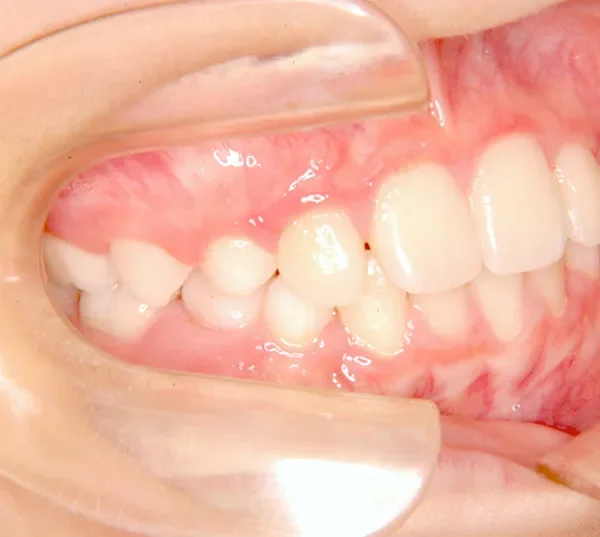

【子供の矯正(一期)】叢生・すきっ歯・永久歯が生える隙間がない・反対咬合・7歳男児【K.S様】

初診時年齢 小学校1年生 (男性) 主訴 すきっ歯・ガタガタ・受け口

診断名 叢生・反対咬合・空隙歯列 装置名

上の前歯が下の前歯より後ろに入って、受け口になっています。

下の歯は永久歯の生えるスペースがないので、オリジナル矯正装置で受け口を治して、永久歯の生えるスペースを作りました。

治療回数19回、2年5ヶ月の治療期間で矯正治療を終了しました。

主訴が改善され、ご満足頂きました。